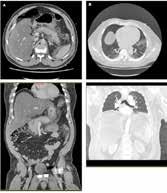

Figura 1.

Evolución pulmonar radiológica en las primeras 24 h, desde la llegada a Urgencias (A), al ingreso en UCI (B), posterior a la intubación orotraqueal y conexión a ventilación mecánica invasiva (C) y tras la canulación de ECMO VV (D). En la imagen D se observa la punta de la cánula de drenaje femoral (punta de flecha blanca) y la de retorno yugular (punta de flecha negra).

Figura 2.

Cortes axial y coronal de TC toracoabdominal en la fase inicial (A y B) y la evolución posterior (C y D). Se puede apreciar la evolución de pancreatitis edematosa (A) a pancreatitis coleccionada (D). A nivel torácico destaca signos de restricción abdominal (B) precoces en probable contexto de hipertensión intraabdominal elevada, con posterior evolución a atelectasia de zonas declives y afectación parenquimatosa heterogénea (D).